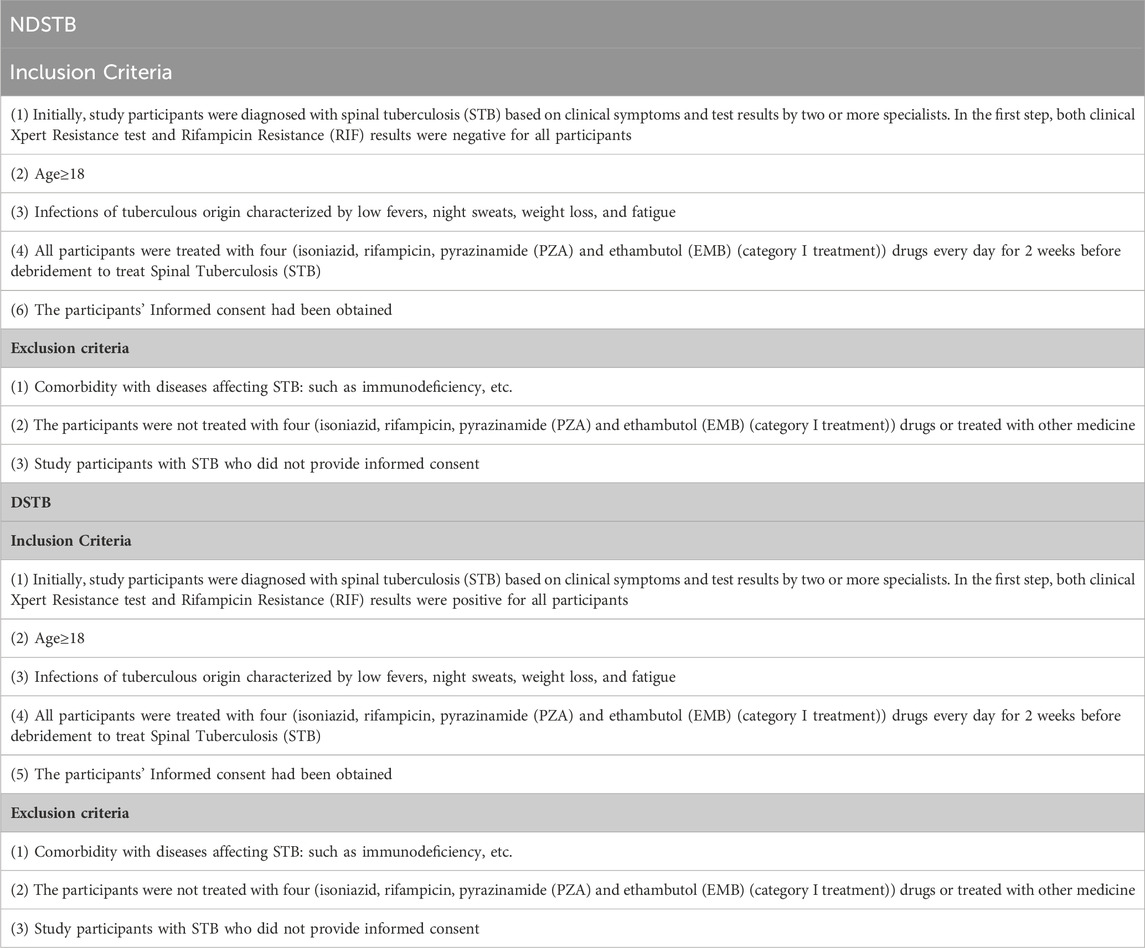

Materials and methodsClinical sample acquisitionWe have secured the proper approval from the Ethics Committee of Hunan Academy of Traditional Chinese Medicine Affiliated Hospital for our study. The investigation involved the examination of forty cases of spinal tuberculosis lesion tissues, collected from the Hunan Academy of Traditional Chinese Medicine Affiliated Hospital. This dataset encompassed 20 patients with non Rifampicin-resistant spinal tuberculosis (NDSTB) forming the control group, and an additional 20 patients with Rifampicin-resistant spinal tuberculosis (DSTB) constituting the experimental group. Surgical removal of spinal tuberculosis lesions was performed on all patients between January 2020 and June 2023, adhering to the inclusion and exclusion criteria outlined in Table 1. Clinical information, including sex, age, history of tuberculosis, regular use of anti-tuberculosis drugs, and T-SPOT.TB test results (Table 2), and the site of spinal infection were meticulously extracted from medical records. After the surgeries, postoperative pathological examinations and culture results unequivocally confirmed the presence of MTB infection in the collected tissue samples. This robust confirmation served as the cornerstone for the study’s investigation into Rifampicin-resistance in spinal tuberculosis.

Table 1. Inclusion and exclusion criteria of DSTB and NDSTB.

Table 2. Baseline characteristics of participants and comparison between NDSTB groups and DSTB group. Participants without a tuberculosis history or a regular use of anti-tuberculosis drugs were not documented. Additionally, any test results that went undetected were not recorded.